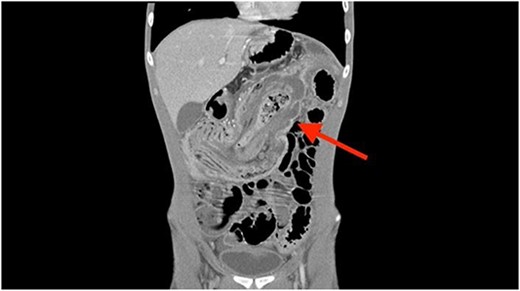

A coronal computed tomography (CT) scan with contrast showed a massive, small bowel to large bowel intussusception involving the majority of the ascending colon and portions of the cecum (Fig. 1). In addition, an axial CT scan showed the classic target sign associated with intussusception (Fig. 2). Due to the patient’s age, a pathologic lead point was suspected, hence surgery was consulted.

Axial CT scan showing characteristic target sign of bowel intussusception.

In cases of suspected intussusception, the initial diagnostic approach should involve an abdominal ultrasound examination. This method is known for its ability to reveal the characteristic bulls-eye or target appearance, although its accuracy is reduced in adults [2, 6]. Even if the ultrasound results are positive or inconclusive, a CT scan should follow, serving as the most accurate diagnostic test for adult intussusception. In adults, the CT scan typically also depicts the bulls-eye or target appearance, as seen in Fig. 2 [2].